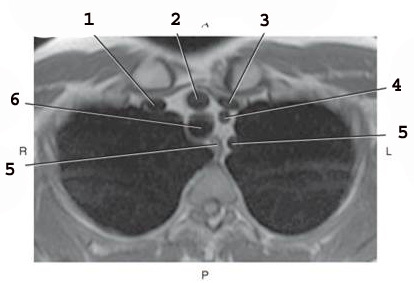

1

L common carotid Artery

2

L subclavian artery

3

AO arch

4

ascending AO

5

SVC

6

Brachiocephalic trunk

7

R subclavian vein

8

R subclavian Artery

9

R common carotid A